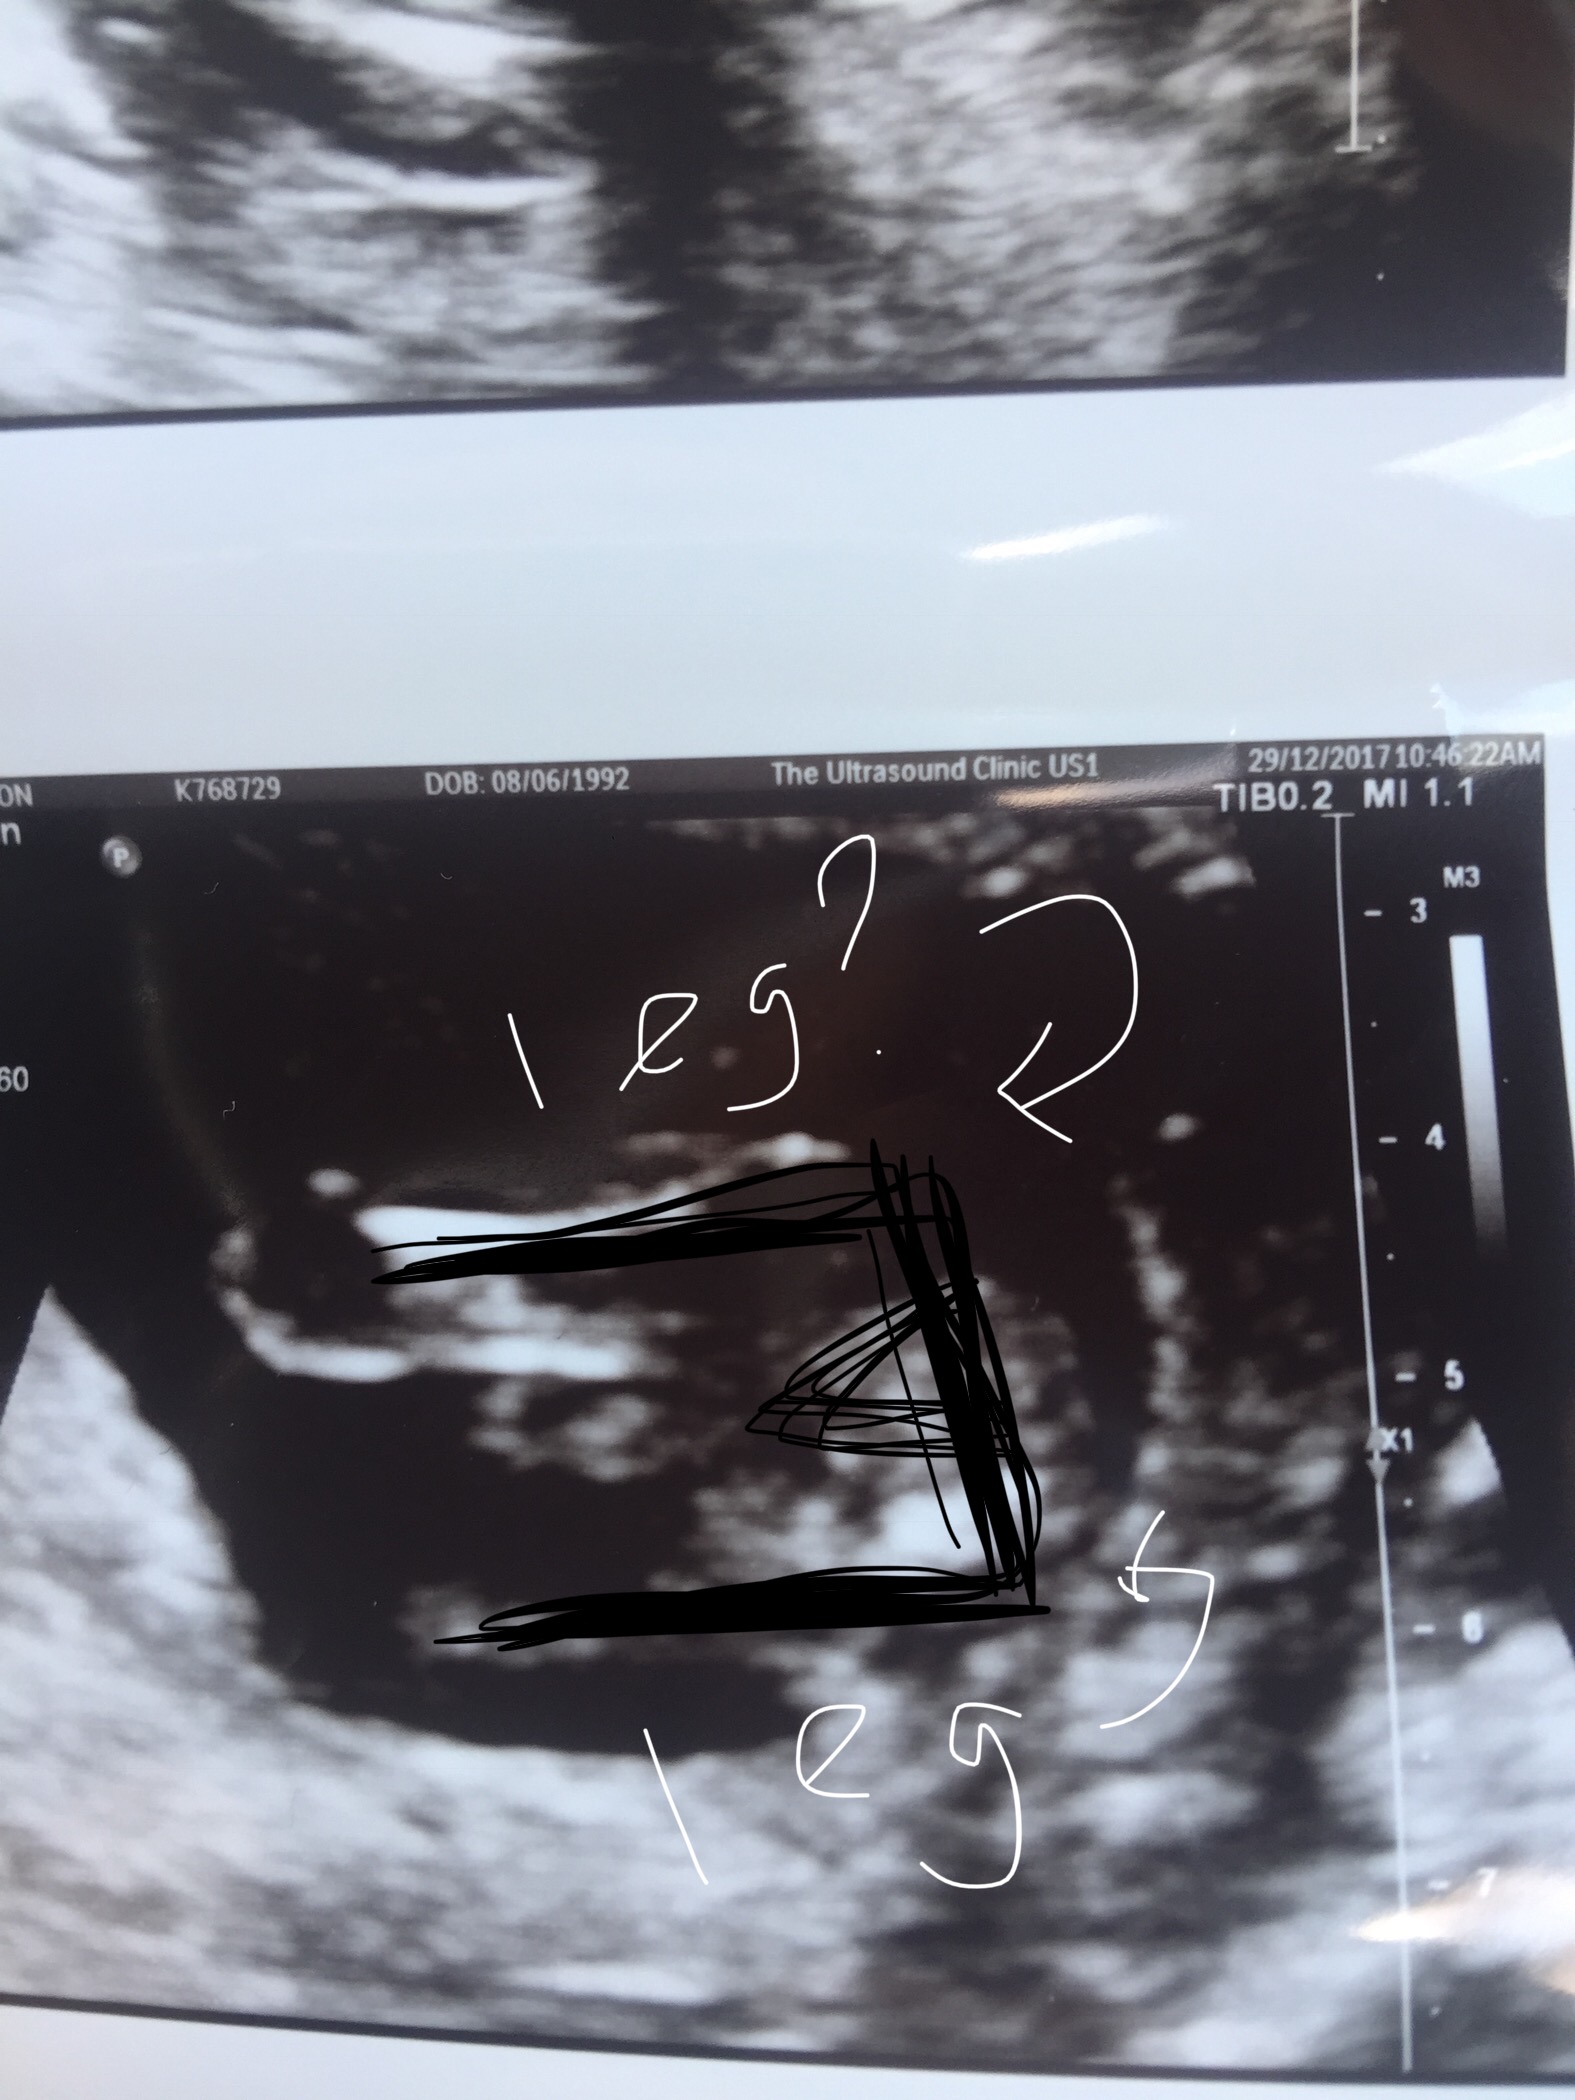

Ok so i had a private scan at 15 weeks and she looked for 2 minutes and said boy but i cant see a definite anything!? I thought i saw lines while she was scanning and this was the only picture of the genitals that she printed and said was the clearest shot!! Anyone know what theyre looking for and can confirm for me anything? Thanks!!